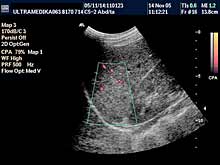

Posebni pregledi:

- Fokalne promene jetre, pankreasa i ostalih parenhimatoznih organa (3D

Sono CT procena i procena vaskularizacije sa Broad band-CD i PD i 3D

CPA modom).

- Broadband-CD i 3D CPA bubrega

- Broadband-CD i CPD renalnih arterija